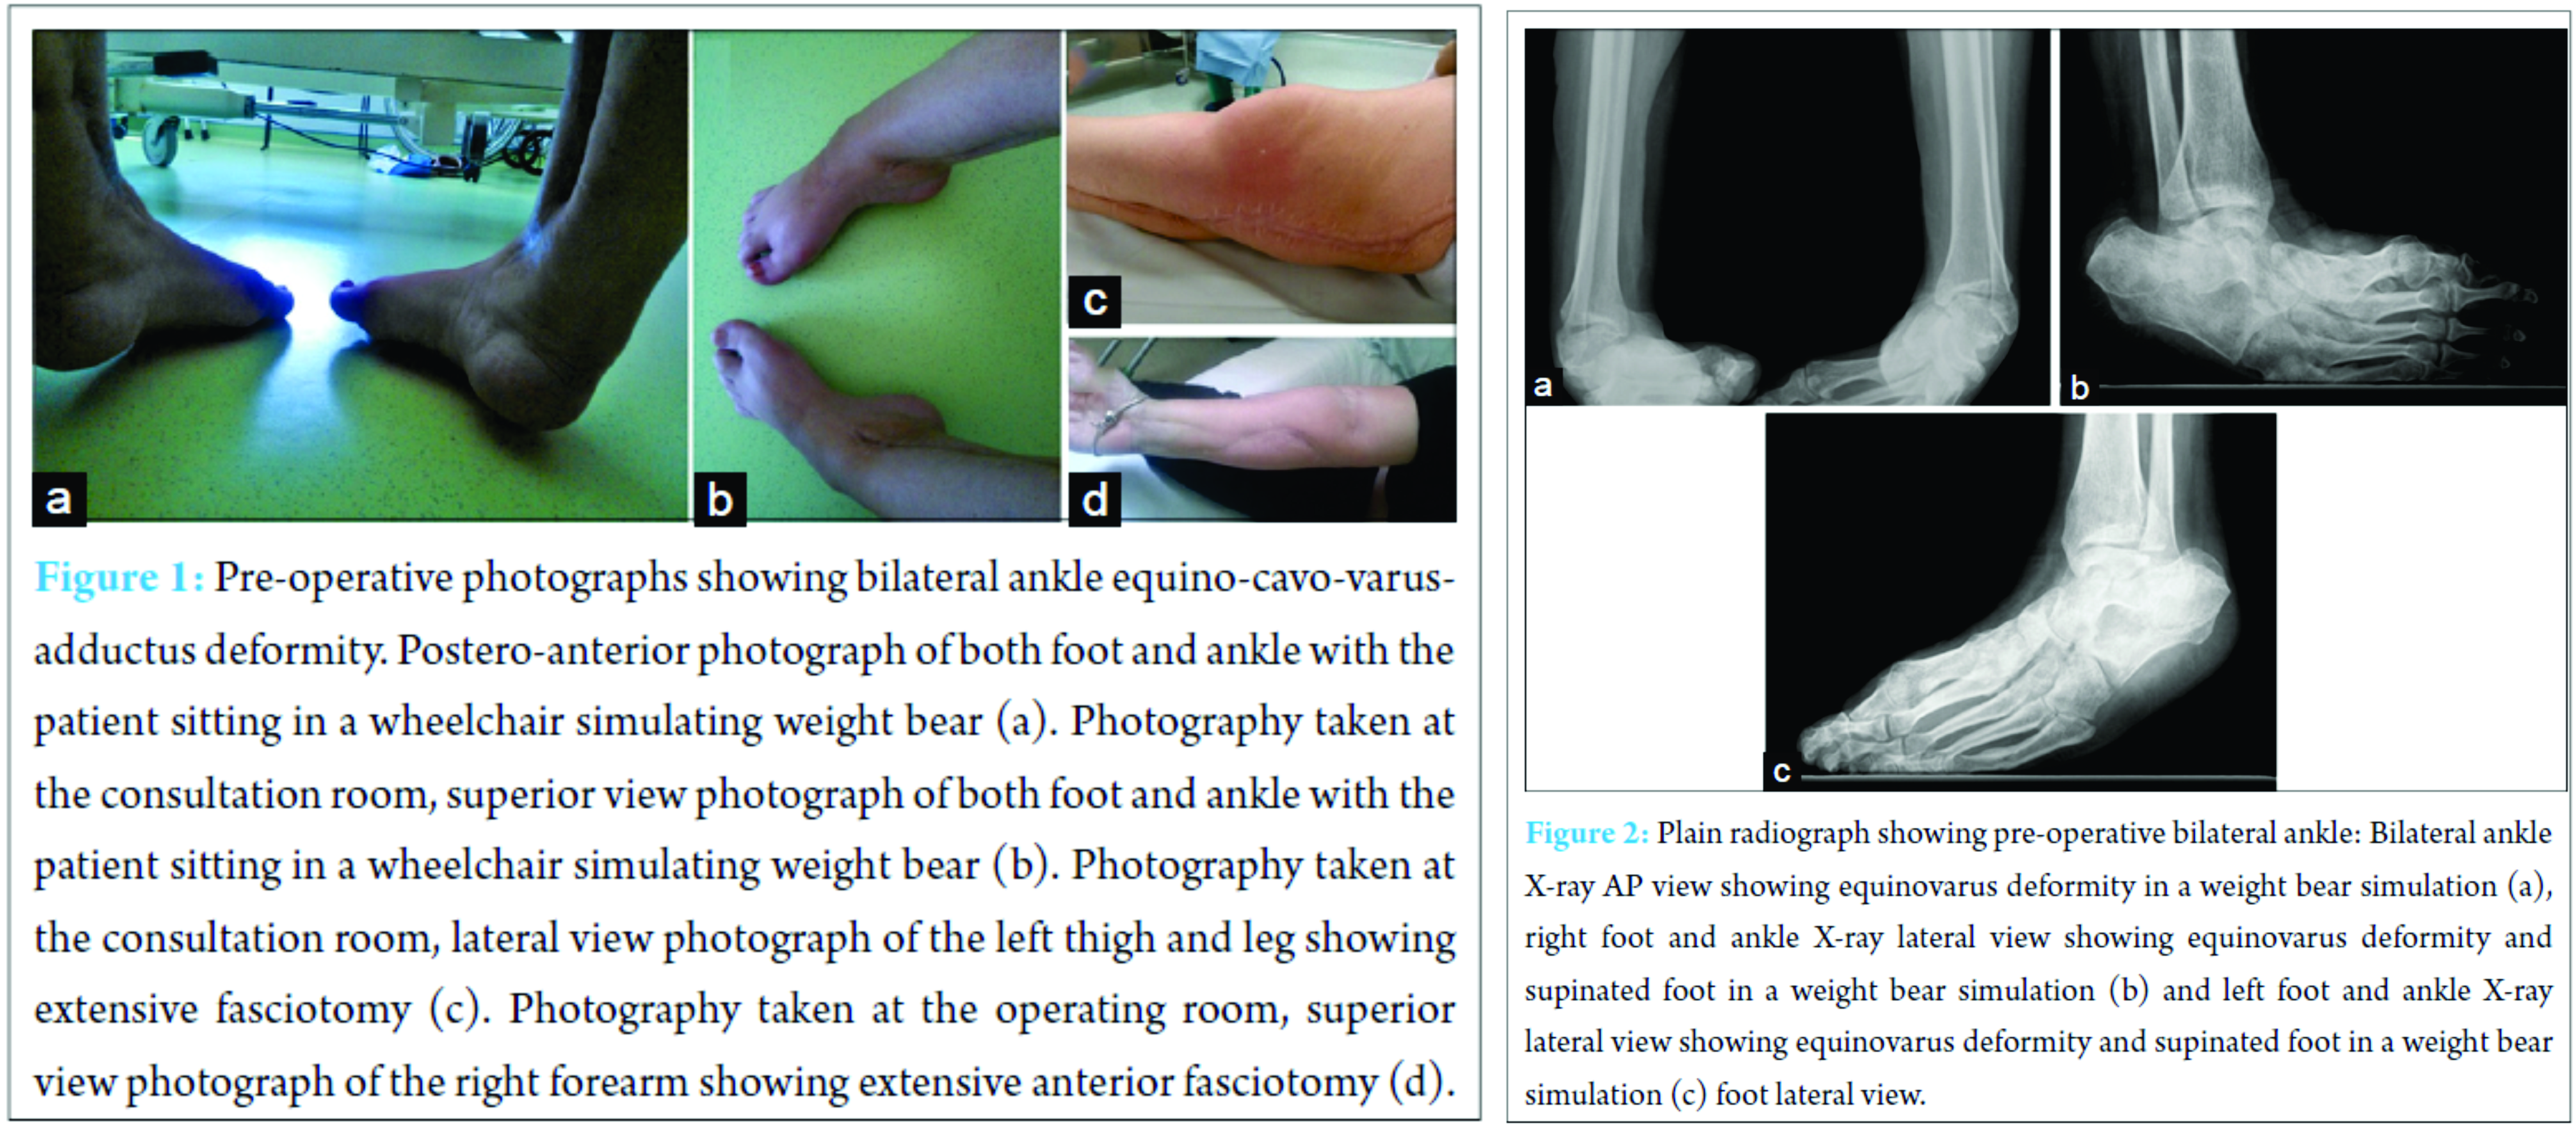

On examination, she presented a bilateral severe stiff equino-cavo-varus-adductus deformity with retraction due to subcutaneous and muscle scarring and neurological deficit. Claw hallux and lesser toes were also present bilaterally. Plantigrade weight bearing was not possible (Fig. 1). American Orthopaedic Foot and Ankle Society (AOFAS) score was 20 points. Plain radiographs showed bilateral equinovarus ankle deformity with supinated feet (Fig. 2). Achilles, posterior tibial, and flexor digitorum longus tendons lengthening were performed by medial approach associated to right tibiotalocalcaneal arthrodesis with a retrograde locked intramedullary nail (PANTA® – IntegraTM) by lateral approach. Distal fibula bone was used as an autograft. At 8 weeks of follow-up, plastic surgery applied a free skin graft over a persistent post-operative medial blister (Fig. 3). Apparent fusion was obtained at 3 months postoperatively (Fig. 4). At 6 months after the initial surgery, fusion surgery of the left ankle was performed in exactly the same fashion. As in the first procedure, clinical and radiological follow-up was done at 2, 6 weeks and every 3 months. Surgical wound dehiscence was the short-term complication and was resolved with dressing changes at 6 weeks post-operative. Fusion was obtained at 3 months postoperatively (Fig. 4).